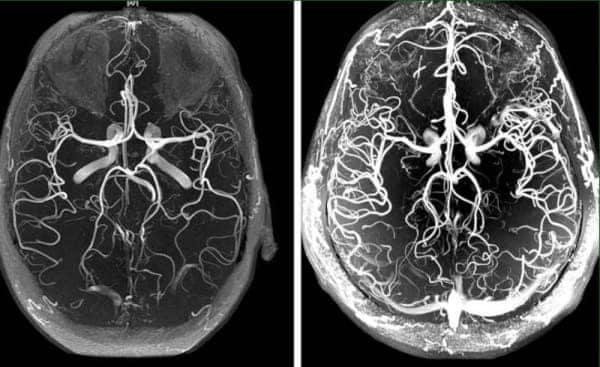

2. Улучшение работы мозга

После курса Cardiodoc на 73% улучшается мозговое кровообращение. Те, кто принимал это средство, отмечают что у них:

- Улучшилась память.

- Нормализовался сон, прошла беспричинная

усталость и слабость.

- Исчез шум и звон в ушах.

- Прекратились

головные боли и головокружения.